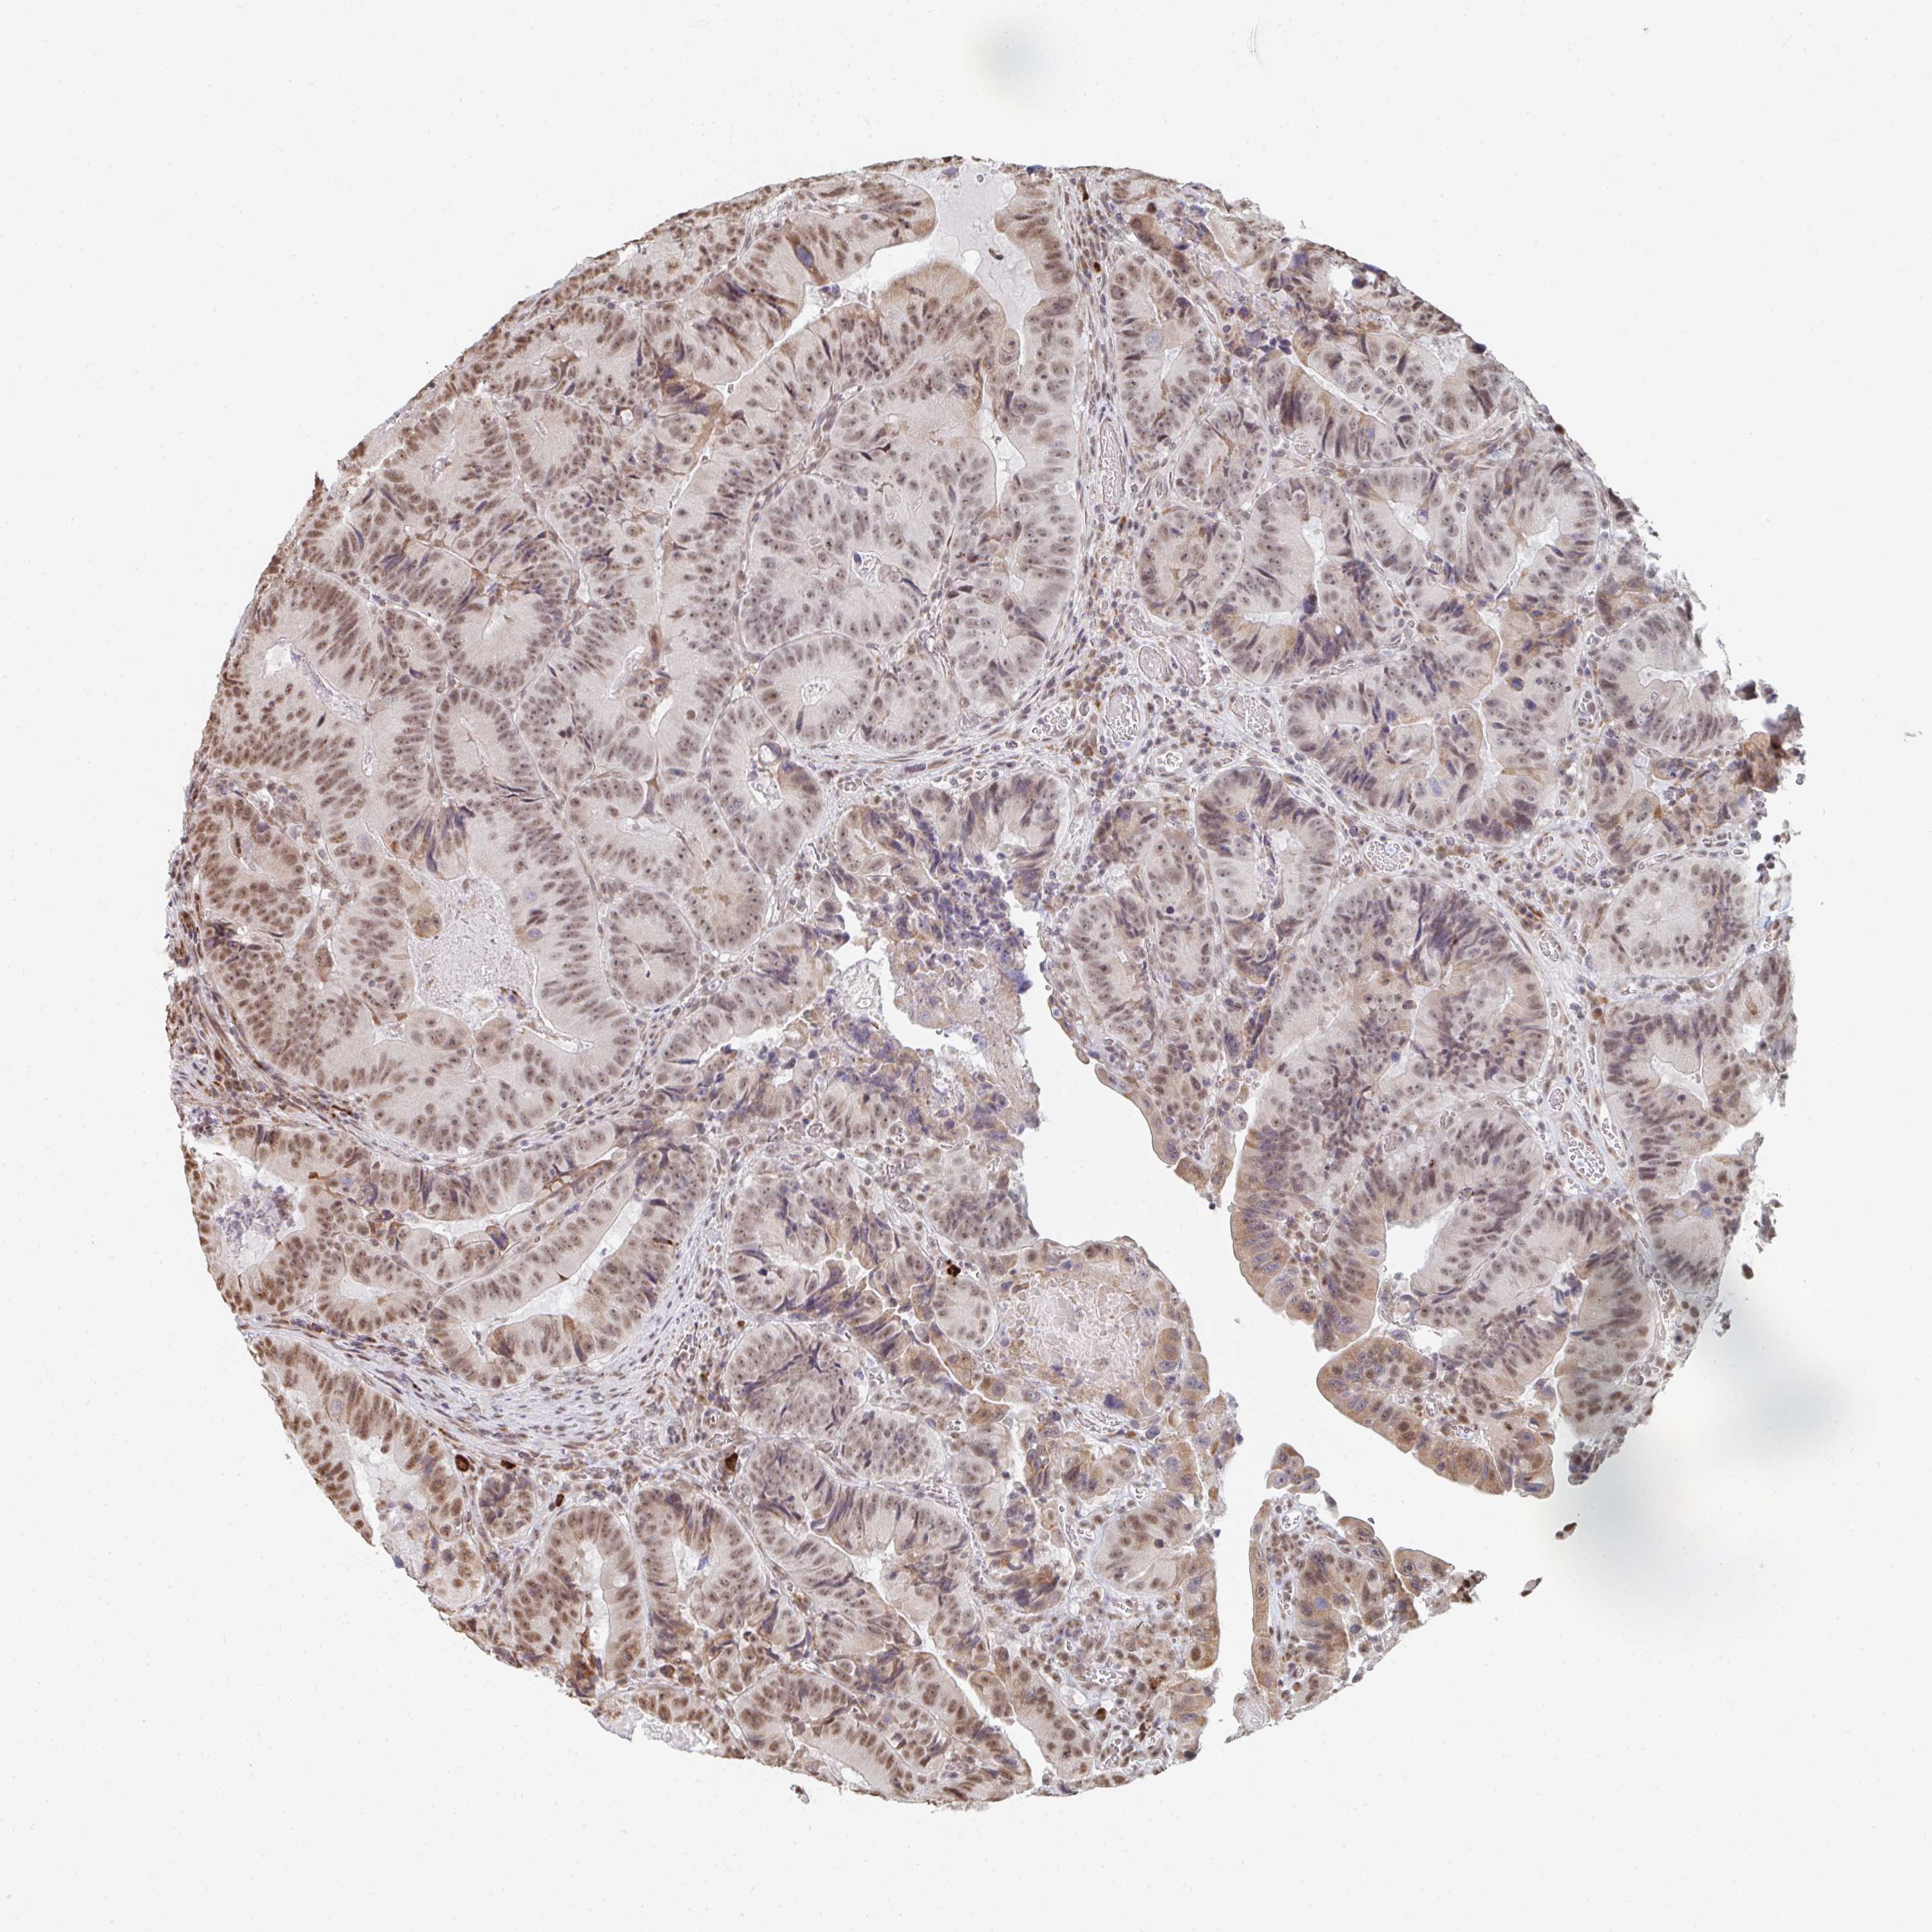

CANCER COLORECTAL CANCER Show tissue menu

Colorectal cancer

Human cancer

Colon adenocarcinoma